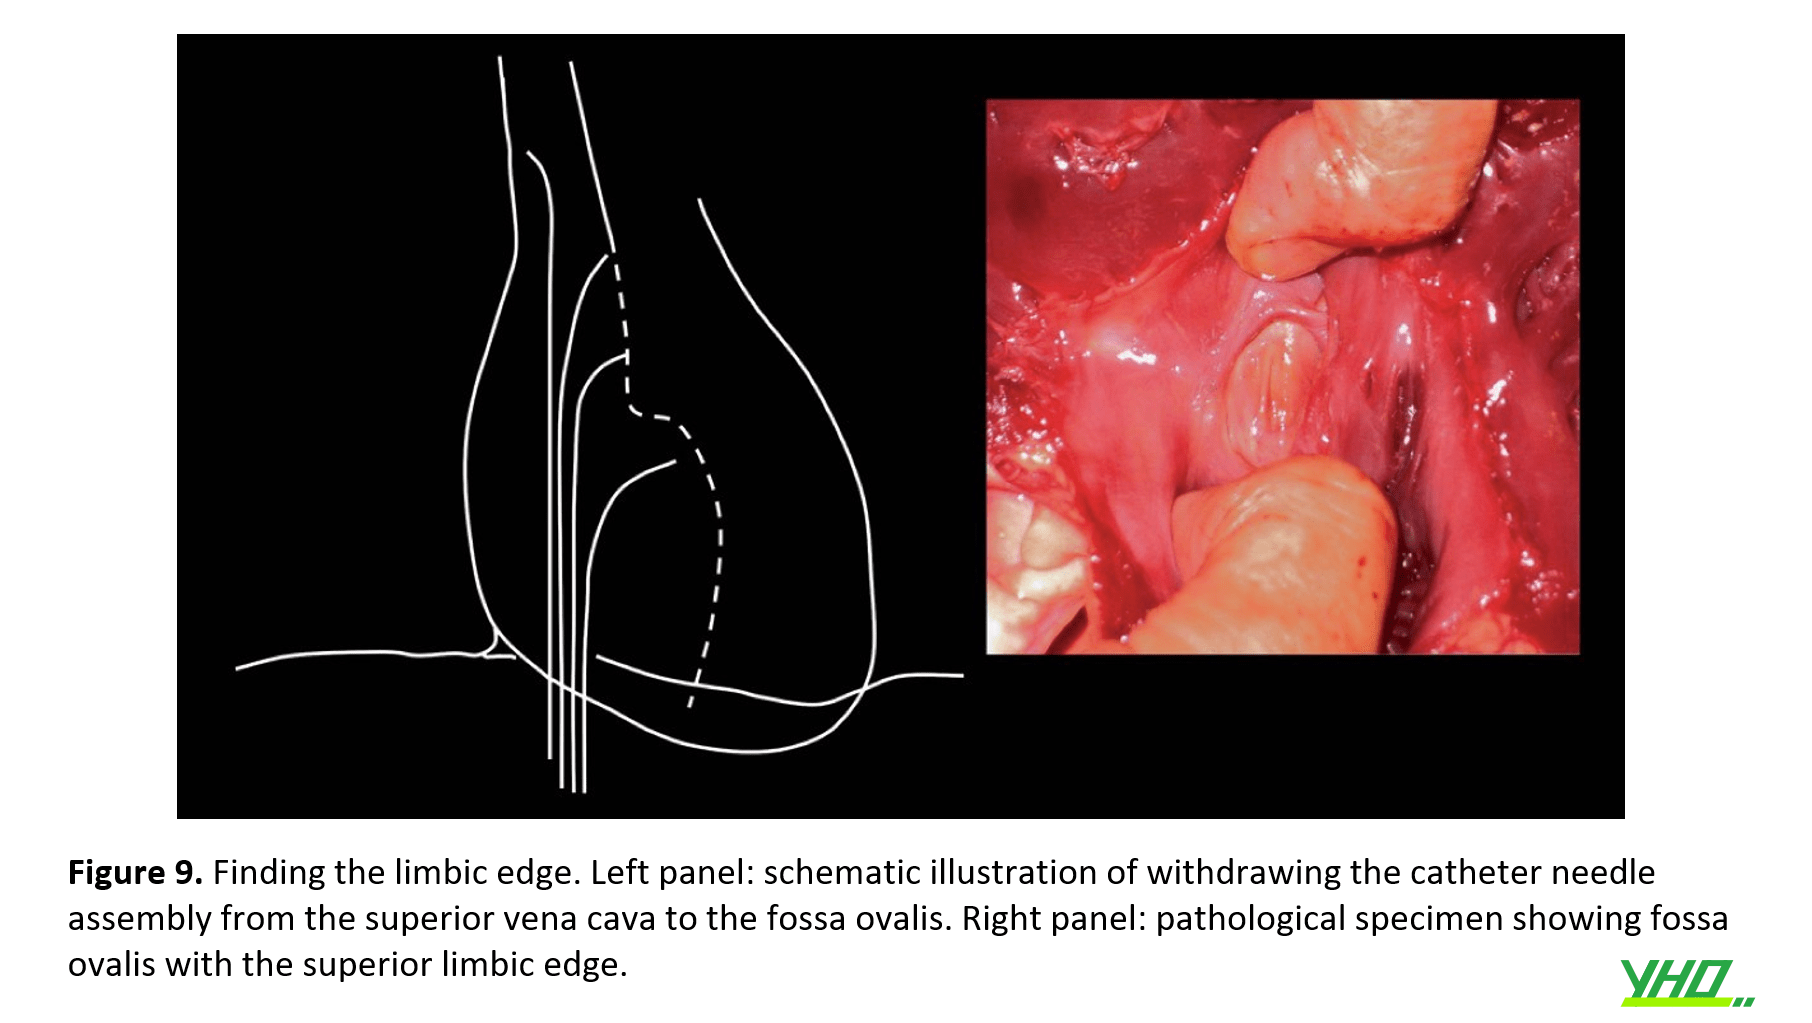

1965, Bloomfield và Sinclair-Smith đã mô tả một cách xác định rìa viền, nơi mà vách ngăn thứ phát nằm trên và hợp với vách nguyên phát.

Ống thông qua guidewire được đưa đến TM chủ trên. Sau đó rút dây dẫn, luồn kim vào ống thông.

Đầu kim hướng về vị trí 4 giờ hoặc đến vị trí 6 giờ đối với nhĩ trái rất dãn. Sau đó, ống thông và kim được rút ra từ từ, đầu ống thông có mũi kim di chuyển về phía trong nhĩ phải.

Khi đầu ống thông vừa xuống dưới rìa hệ viền, có thể nhìn thấy và/hoặc cảm thấy khấc chuyển động nhẹ, nghĩa là đầu ống thông đã đi vào hố bầu dục và đã tới khu vực an toàn để đi qua.(hình 9)